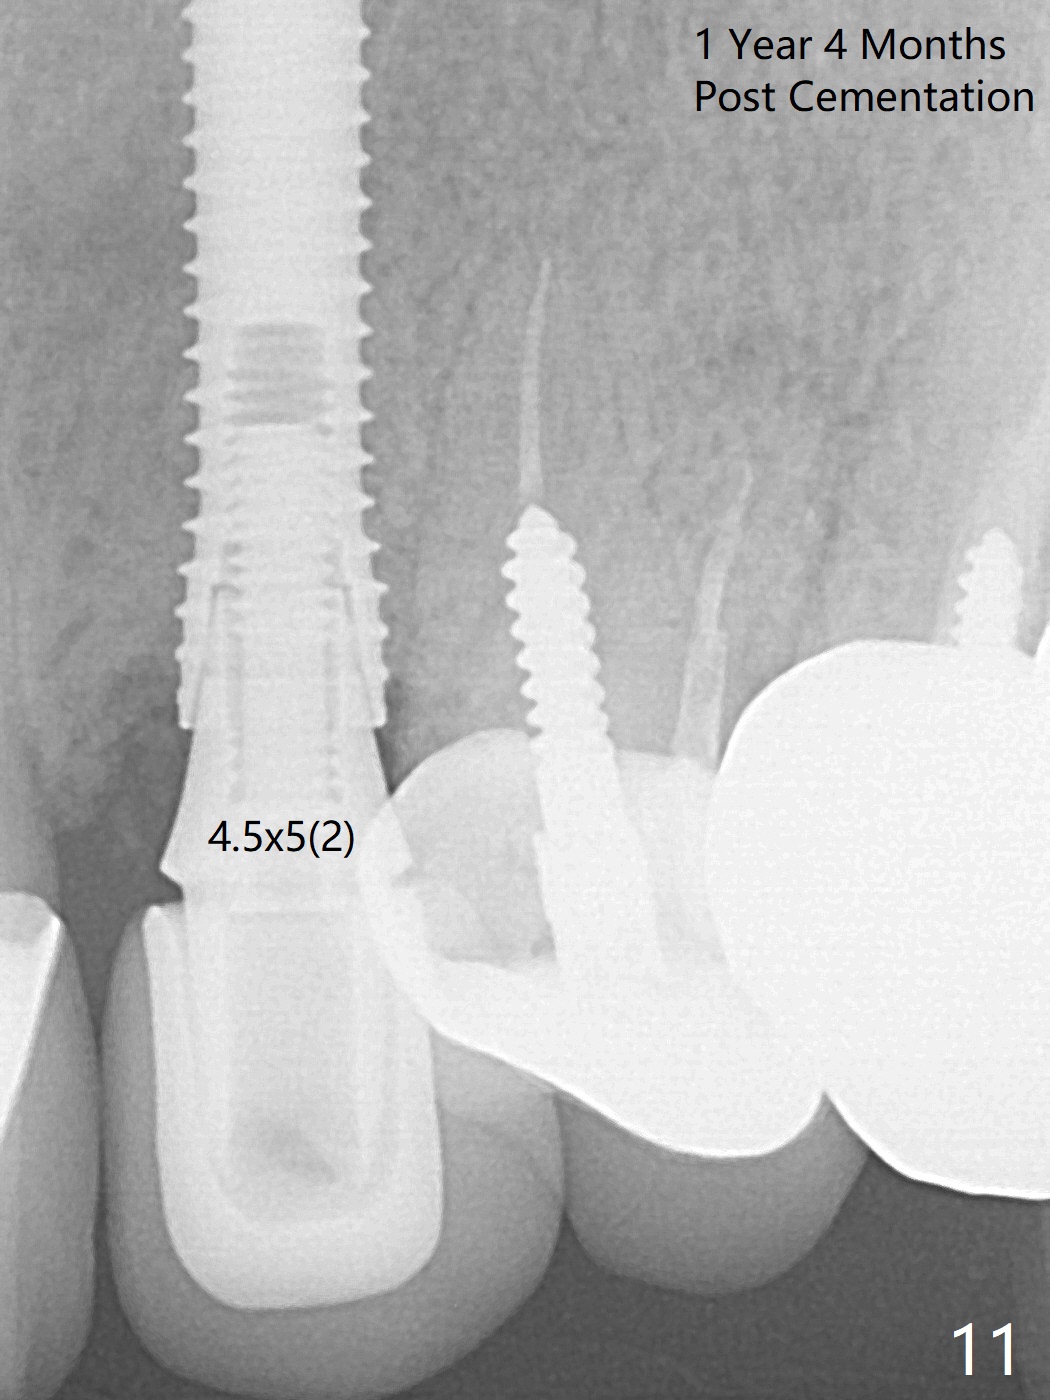

In spite of severe apical infection (Fig1,2 *), a thin narrow strip of the buccal plate (arrowheads, corresponding to the keratinized gingiva) is present when the tooth #11 is extracted. The thin bone keeps the bulging alveolus, i.e., reservoir for bone graft (Vanilla/Osteogen Fig.4 *) after placement of a 3.8x16 mm implant (Fig.3,4). A 4.5x1 mm temporary abutment, placed and trimmed for an immediate provisional, seems to be short in cuff. When an implant is placed deep to prevent periimplantitis, the cuff should be longer, i.e., 3 mm. X-ray should be taken for the depth confirmation after temporary abutment placement. Eight days postop, the mesial gingiva erythema has subsided (Fig.5 < (P: provisional)), while the apical swelling is no longer tender and most likely due to packed bone graft (*). Panoramic X-ray taken 2 weeks postop shows the clearance from the nasal cavity or the maxillary sinus (Fig.6). While the hard tissue around the implant seems to be healthy 5 months postop (Fig.7), the soft tissue is not (Fig.8). The temporary abutment is changed to a cemented one (4.5x5(2) mm) for impression (Fig.8). Since the neighboring crowns are PFM (Fig.6), the new crown will be made of the same material for shade match. Indeed PFM helps shade match in this case as well (Fig.9,10). Switching abutments (from temporary to cemented) makes it difficult to seat the crown. Post cementation X-ray leaves record for future contact loosening. The buccal gingiva remains erythematous associated with open margin (Fig.11 >) 1 year 4 months post cementation. There is no obvious bone loss 1 year 4 months post cementation (Fig.12). It appears that the crown and abutment need to be changed. Although the gingival margin remains erythematous, the gingival hemorrhage is basically lacking due to better oral hygiene during Shelter at Home (1 year 9 months post cementation, Fig.13). Change in abutment and crown will be conducted post coronavirus pandemic. In fact the abutment is incompletely seated (Fig.14 <). In addition, the tooth #12 is symptomatic with PARL associated with the buccal root (*). CBCT indicates possible buccal root fracture (Fig.15,16 ^) and loss of the buccal plate (Fig.16 <).